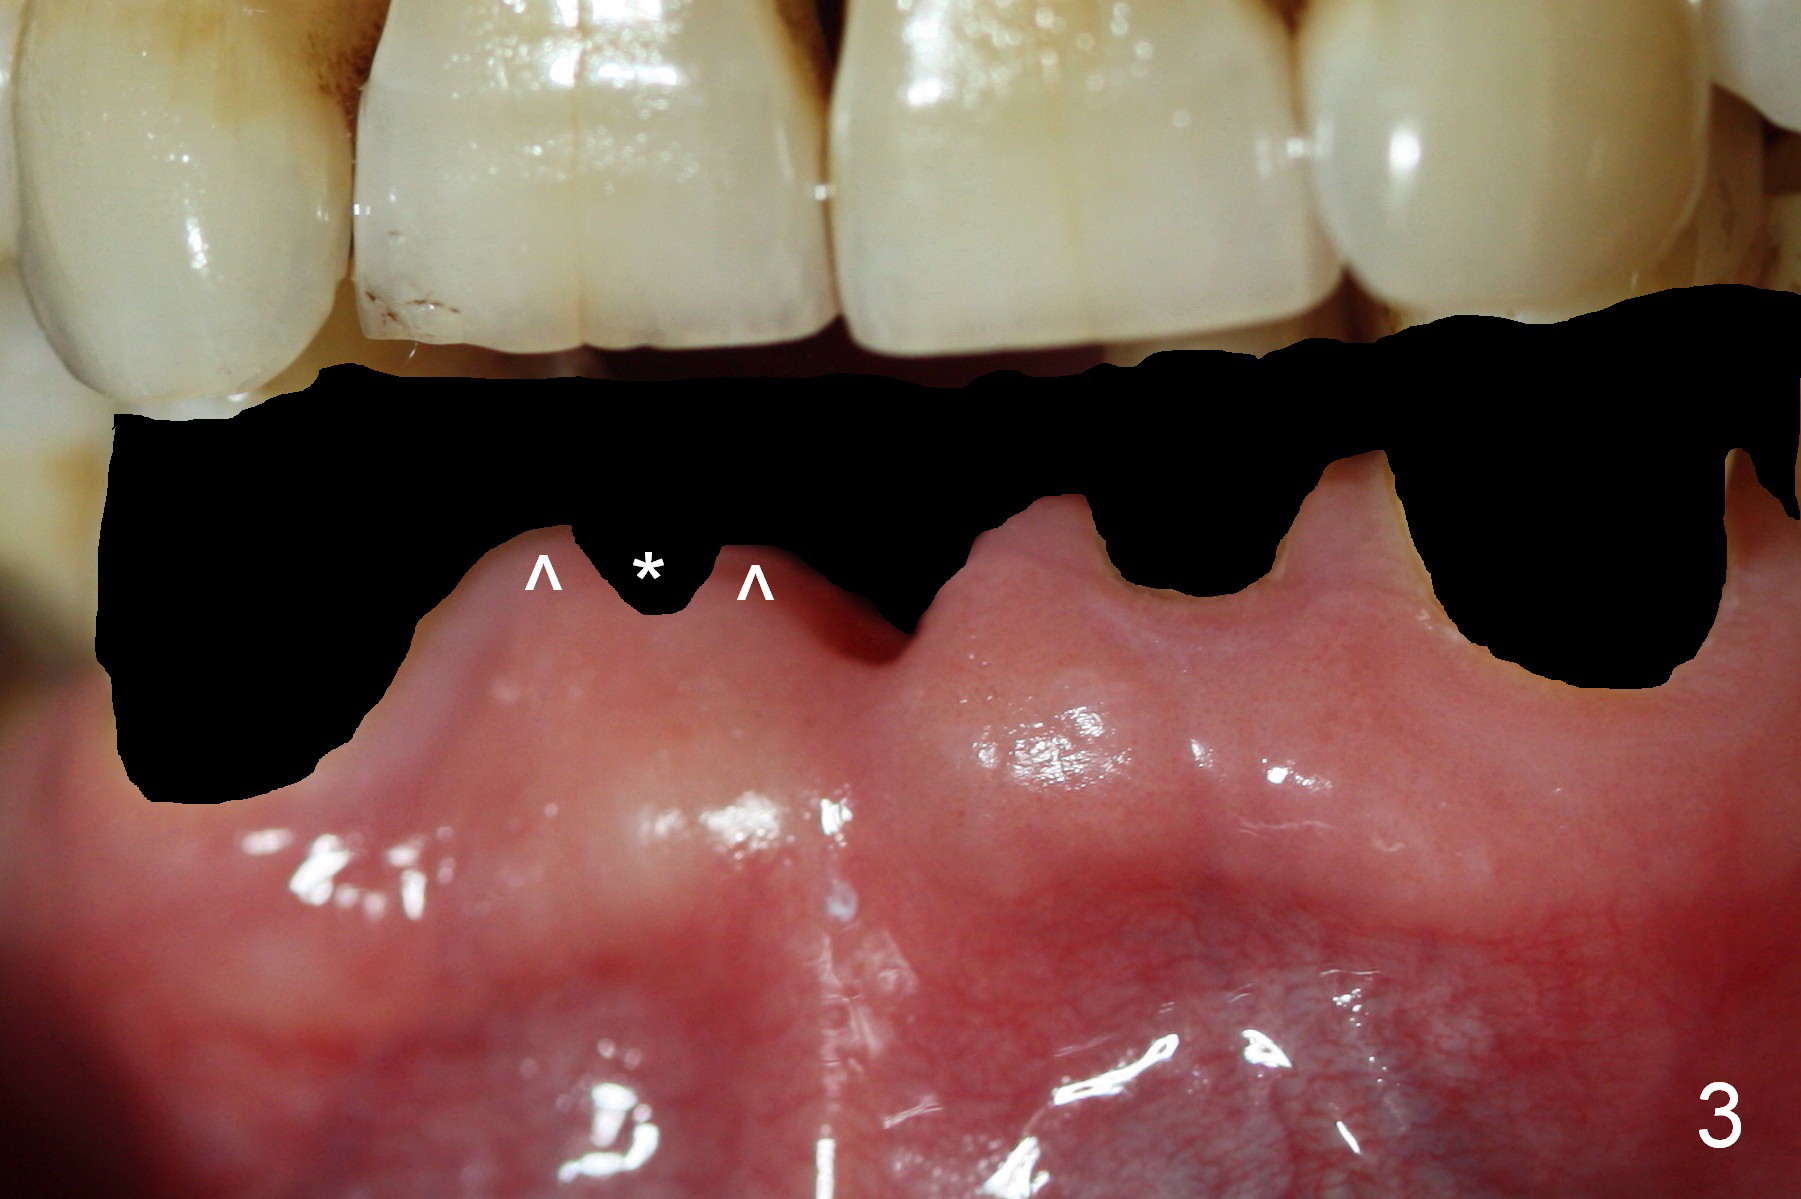

The teeth give the gingiva scallop shaped (Fig.1, 2). The scallop is less where the tooth is absent (Fig.2 *). The scallop must have been distinct when the tooth is just extracted with prominent papillae (Fig.2,3 ^).

One of the functions of an immediate provisional is to maintain and create the valleys and peaks of the gingival morphology (Fig.4-6). When the wound heals initially, the provisional should be modified (Fig.5 yellow curves) to push the gingiva aside (Fig.6 arrows) to create oval pontic and papillae (Fig.5).